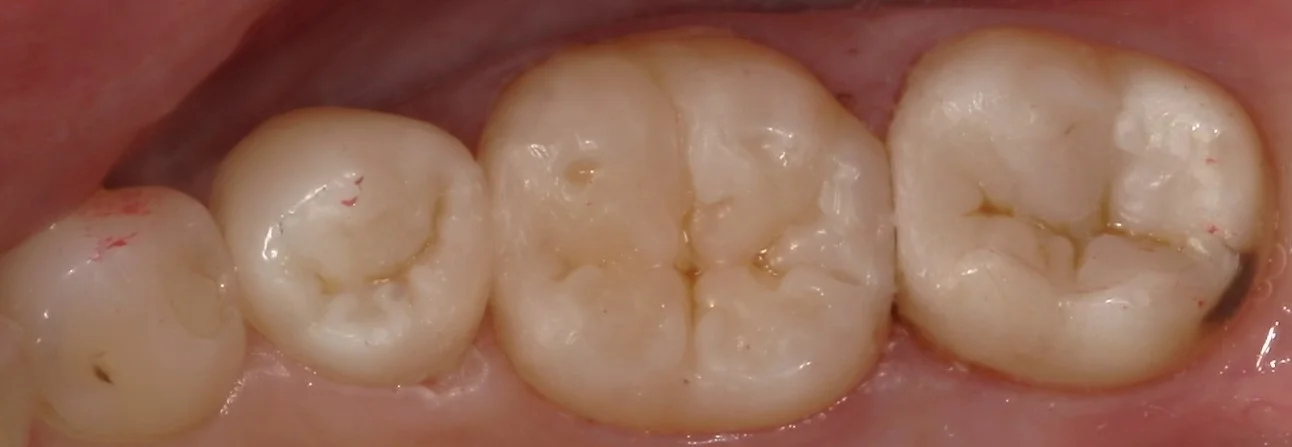

では、虫歯を取りきった写真に移ります。

それがこちらですね。

本来の歯の色が綺麗に出たのが分かるかと思います。

歯の着色部分については取る取らない先生の考え方によって変わってくるのですが・・・

私は基本的には取りきれるなら取りきるべきという考えです。

というのも、着色部分は接着力が優位に落ちてしまうというデータもあるので、それに準じて取れるだけ取るようなスタイルに落ち着いている感じですね。

一番右側の歯の端っこに着色が残っていますが、これについては内面に虫歯は出来ておらず、本当に表層のみの着色でしたので、予後に影響がないと判断しました。

この部分の歯が残っているかどうかで、今後この歯に対する破折のリスクも変わってきますので、見た目の為だけに取るのはもったいないと思いました!

そして、詰め終わたのがこちらの写真です。

長時間の処置だったため、乾燥しており、詰めた部分が浮いているような感じになっていますが、1週間もすると歯に水分が戻り、違和感が無くなってきます。